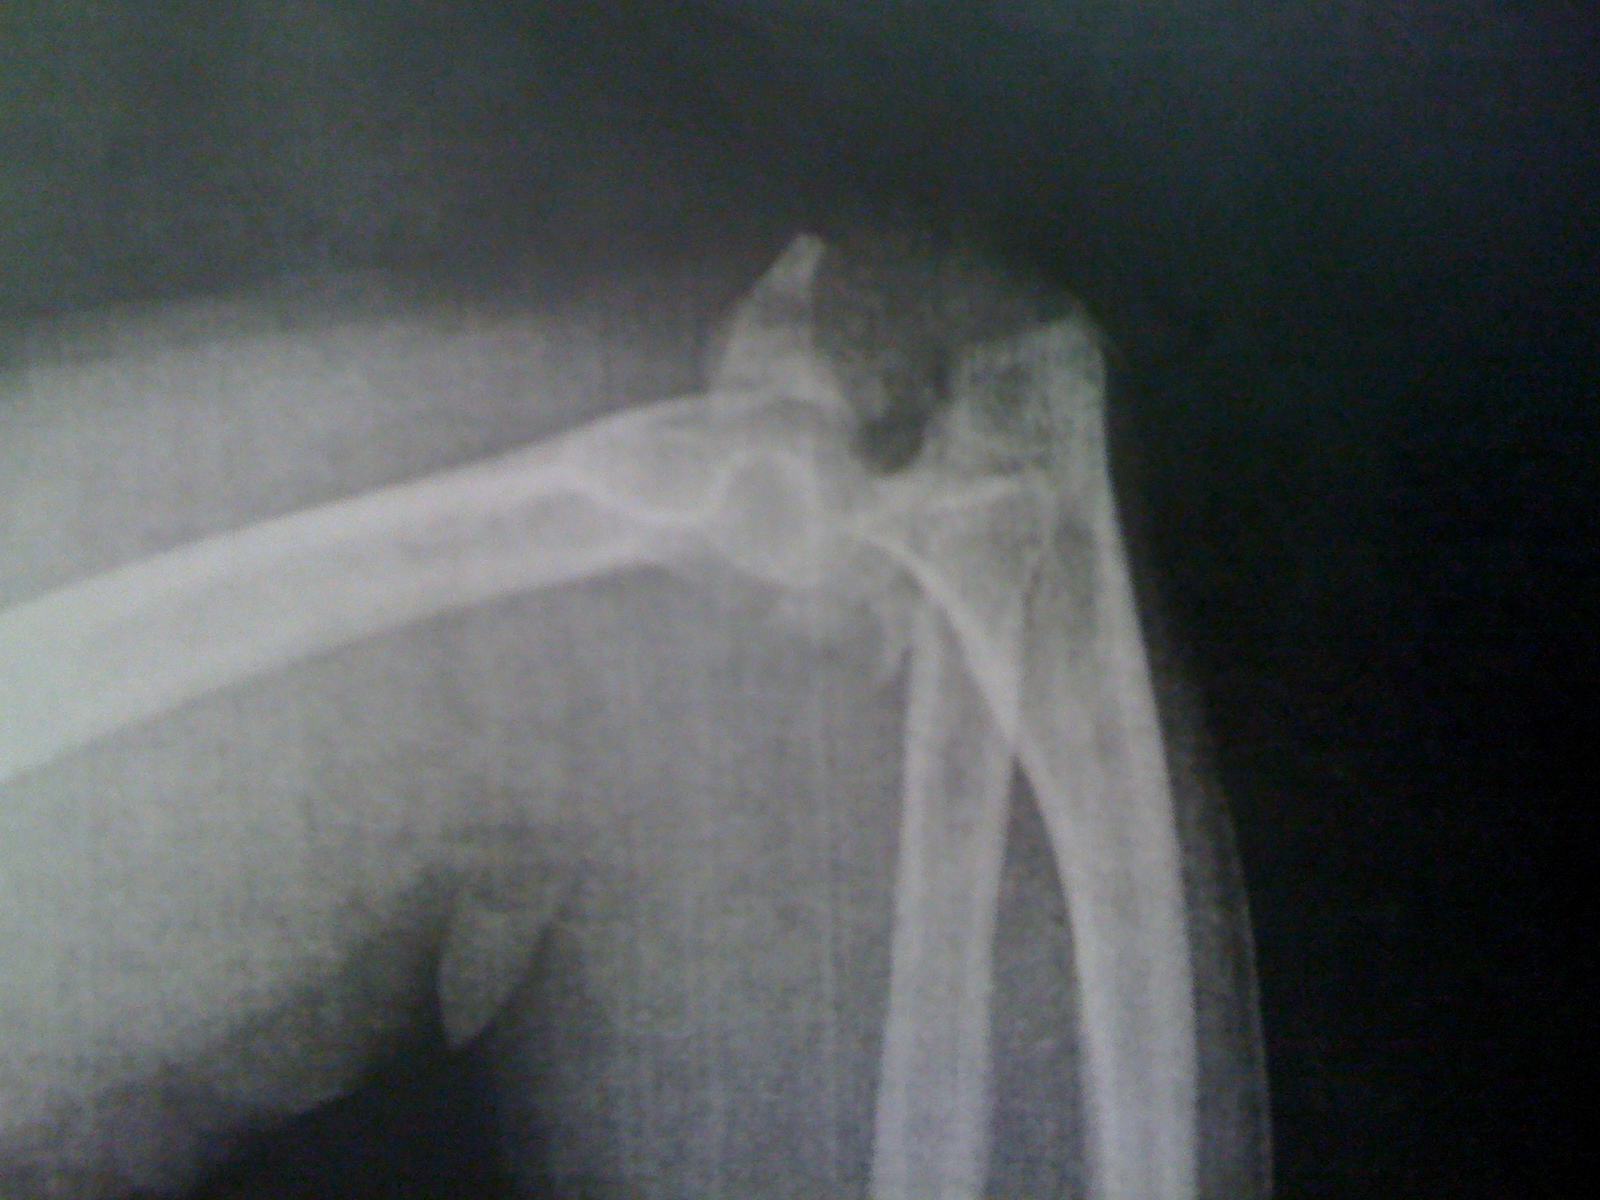

Diana rushed over from Darlington and took me to the ER at McLeod. It was there that John Ulmer was on call. (John is a Physician’s Assistant with McLeod Orthopedics and one of our former youth). John did an incredible job explaining what he saw on the X-Rays and walking us through. John reset my left arm and splinted both arms. The surgeon told us that when he first saw the films, he thought I had been in a car accident. He said that people don’t normally break their arms like I did from a fall. Surgery was scheduled for Friday morning on my left arm and I was admitted to the 11th floor at McLeod.

The surgery went well, but there is a long recovery and rehabilitation period ahead for my left arm. The doctor says we really won’t know how close to full use of my arm we can achieve until it heals and I go through some therapy. Another surgery is in my future, but we don’t know if it will be days, months or years from now. The good news is that they are not planning to cast my right arm. The doctor thinks we will be able to get by with a hinged brace since the radial head in that arm is only cracked and the elbow is just chipped.